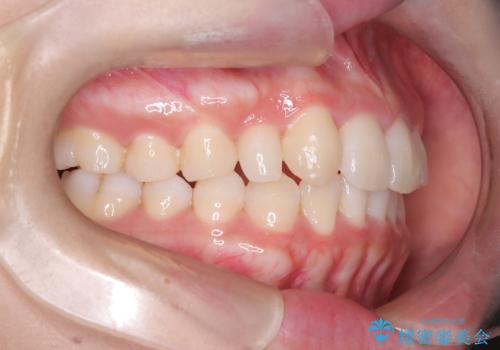

【インビザライン】八重歯が気になる

- 乳歯を抜歯してスペースを確保し八重歯の改善を行いました。

インビザラインをしっかり使用していただいたので、きれいな歯並びになりました。